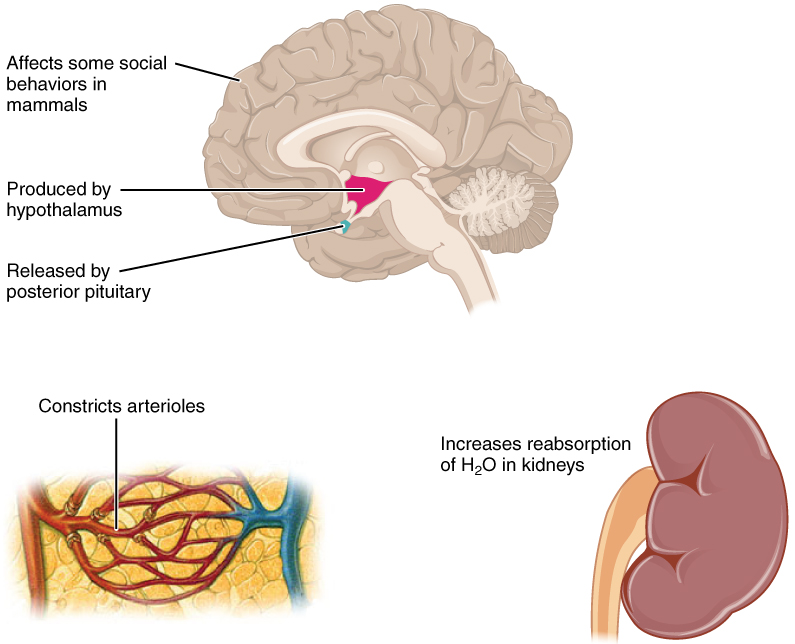

Location of the kidneys there are two kidneys which lie retroperioneally in the lumbar area. The angiotensinconverting enzyme converts angiotensin i to angiotensin ii which stimulates the adrenal cortex to secrete aldosterone a hormone that is involved in increasing blood pressure. The basic anatomy and physiology of the kidney how kidney function changes through life the anatomy of the kidney the kidneys are comple x and beautiful organs.

A decrease in blood pressure results in the release of renin which converts angiotensinogen to angiotensin i.